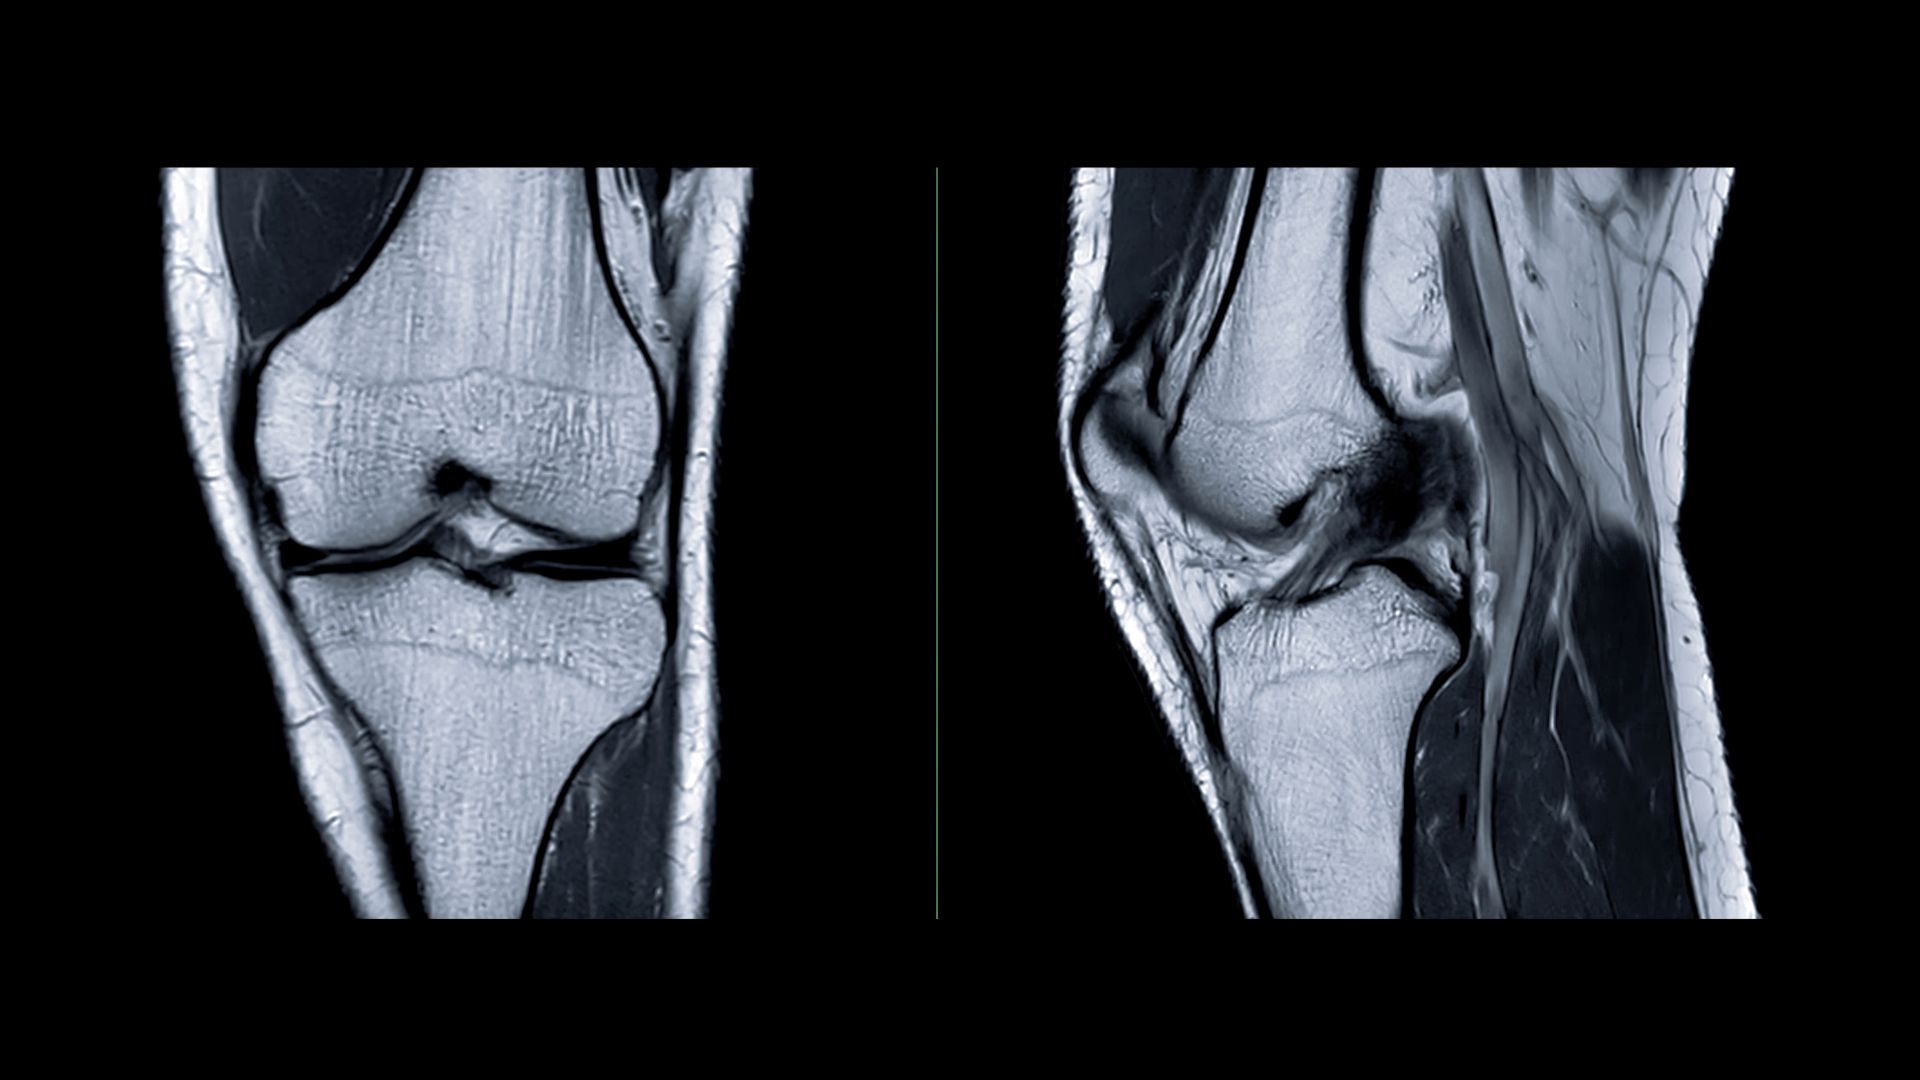

Levicept Ltd will present new findings from its Phase 2 trial of LEVI-04, a first-in-class neurotrophin-3 inhibitor, at the American College of Rheumatology’s annual meeting, ACR Convergence 2025, held from 24–29 October in Chicago. The data highlight dose-dependent reductions in bone marrow lesion presence and area in patients with osteoarthritis (OA), alongside improvements in patient-reported symptoms, including pain.

The Phase 2 study was a multiarm, multicentre, randomized, double-blind, placebo-controlled trial enrolling 518 participants with knee osteoarthritis and associated pain and disability (ClinicalTrials.gov ID: NCT05618782). Previous results from the study confirmed that LEVI-04 met its primary efficacy endpoint, demonstrating significant analgesic effects and a favourable safety and tolerability profile.